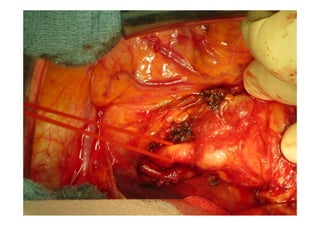

52 jährige Patientin

Gewichtsverlust

Adynamie

Nachtschweiß

Immer wieder Fieber über 12 Monate

Raucherin > 30 packyears

Lungensequester mit

infradiaphragmaler arterieller

Blutversorgung